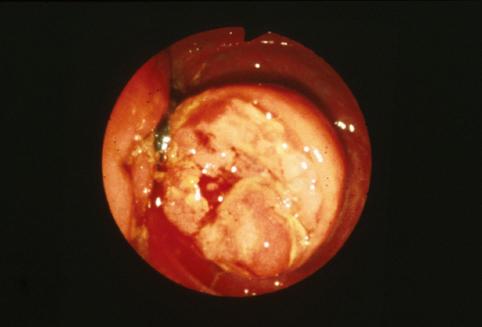

疾病(病理主体)的分类恶性上皮性肿瘤/腺癌

部位(按器官分)大肠/阑尾

检查方法内窥镜

肿瘤的肉眼分类2型(溃疡局限型)/

肿瘤最大直径25~29

肿瘤的深度s(a)